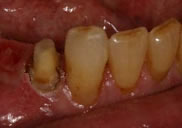

before

Before Crown Lengthening

This tooth required crown lengthening to provide enough tooth surface for a restoration